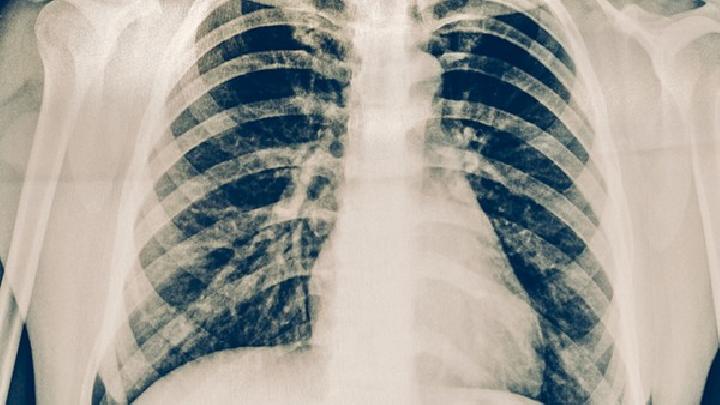

肺栓塞(pulmonaryembolism,PE)是以各种栓子阻塞肺动脉系统为其发病原因的一组疾病或临床综合征的总称,如肺血栓栓塞症、脂肪栓塞综合征、羊水栓塞、空气栓塞等。肺动脉发生栓塞后,若其支配区域的肺组织因血流受阻或中断而发生坏死,称为肺梗死。